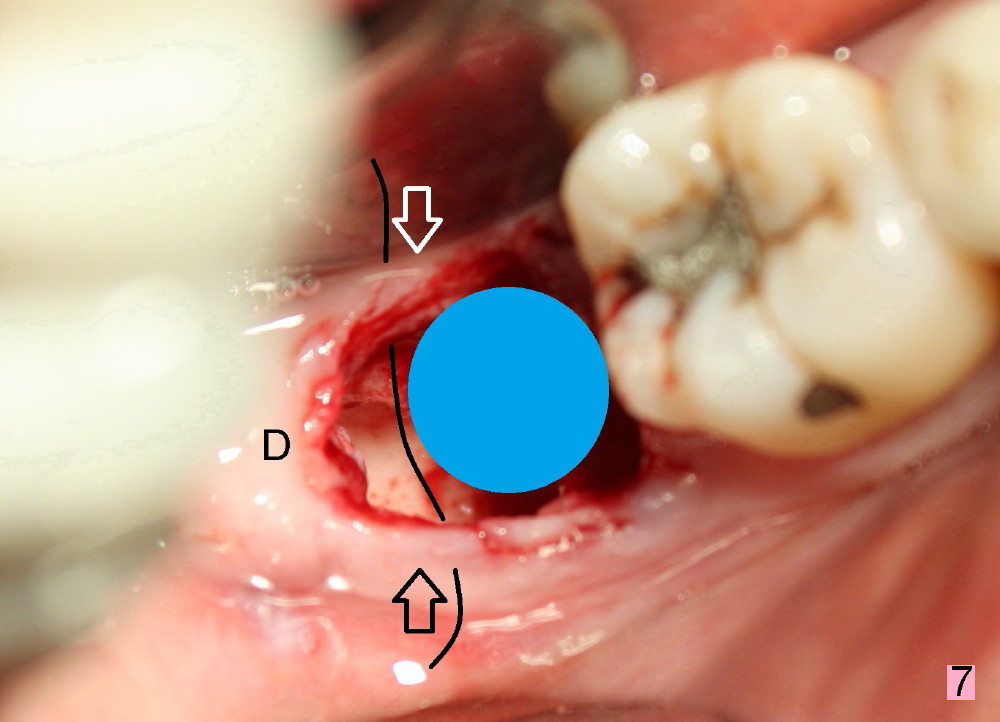

The patient returns 22 days postop (Fig.8-10). The gingiva heals around the implant. There is excess lingual gingiva (Fig.9,10 *), which should recede gradually. Fig.7 is an illustration (from Fig.4) to show how the socket is closed.. A suture is placed (black line) to approximate buccal (black arrow) and lingual (white arrow) gingiva distal to the implant (blue circle).